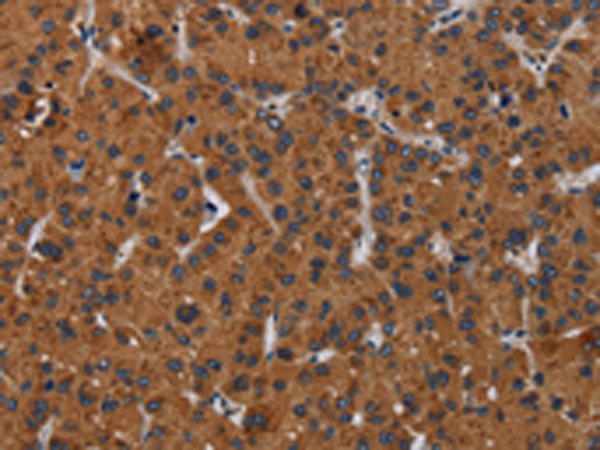

分类: 科研抗体货号: P08427别名: IDH; IDP; IDHM; IDPM; ICD-M; D2HGA2; mNADP-IDH应用: WB,IHC反应种属: Human, Mouse, Rat